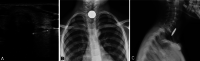

Purpose: Foreign body (FB) ingestions represent a common problem in children. History and physical examination are commonly not enough to diagnose a foreign body ingestion; therefore, conventional radiography is routinely used to detect them. Point-of-care ultrasound is widely used in the emergency department for several diagnostic applications but there are few articles describing the possibility to use point-of-care ultrasound to detect ingested foreign bodies, and the necessary training to get competent in this application. The main objective of this paper is to illustrate the use of point-of-care ultrasound (POCUS) to detect ingested foreign bodies. The secondary objective is to describe a limited training, necessary for emergency pediatricians, to obtain this skill.

Methods: This is a case series of eight pediatric patients who presented to the pediatric Emergency Department (ED), with suspected ingestion of FB, and were assessed with POCUS. Physician sonographers were two pediatricians and three residents in pediatrics working in two Italian Pediatric EDs. All sonographers participated in a 2-day POCUS workshop which included the most common pediatric POCUS applications.

Results: POCUS, performed by emergency pediatricians who participated to a limited training, allowed to always identify the foreign bodies ingested.

Conclusions: We demonstrate that an appropriate and limited training allows pediatric emergency physicians to correctly identify foreign body in the esophagus or stomach. Point-of-care ultrasound in foreign body ingestion in the Emergency Department may allow to prioritize the escalation of care in children and it can contribute to reduce the time to endoscopic management when needed.